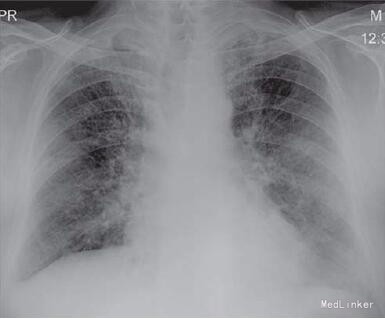

查体:杵状指,双肺吸气末捻发音。余未查见特殊。 辅查:血常规、肝肾功均正常。锻炼前后(步行实验)氧饱和度和脉搏分别为95/88和89/98,超声心动图提示I级舒张功能不全,左室射血分数为55%,肺动脉压为25mmHg,肺功能提示混合性障碍,FVC为2.36(预计值为69%),FEV1为1.63(预计值为56%),FEV1/ FVC比为68,胸片提示双肺网状影(图1),高分辨率CT(HRCT)提示小叶间隔增厚及蜂窝状影(图2). 支气管肺活检显示间质性纤维化伴炎性浸润,有慢性炎细胞浸润。炎性细胞间的巨噬细胞充满色素,普鲁士蓝铁特殊染色为阳性,提示铁末沉着病(图3)。